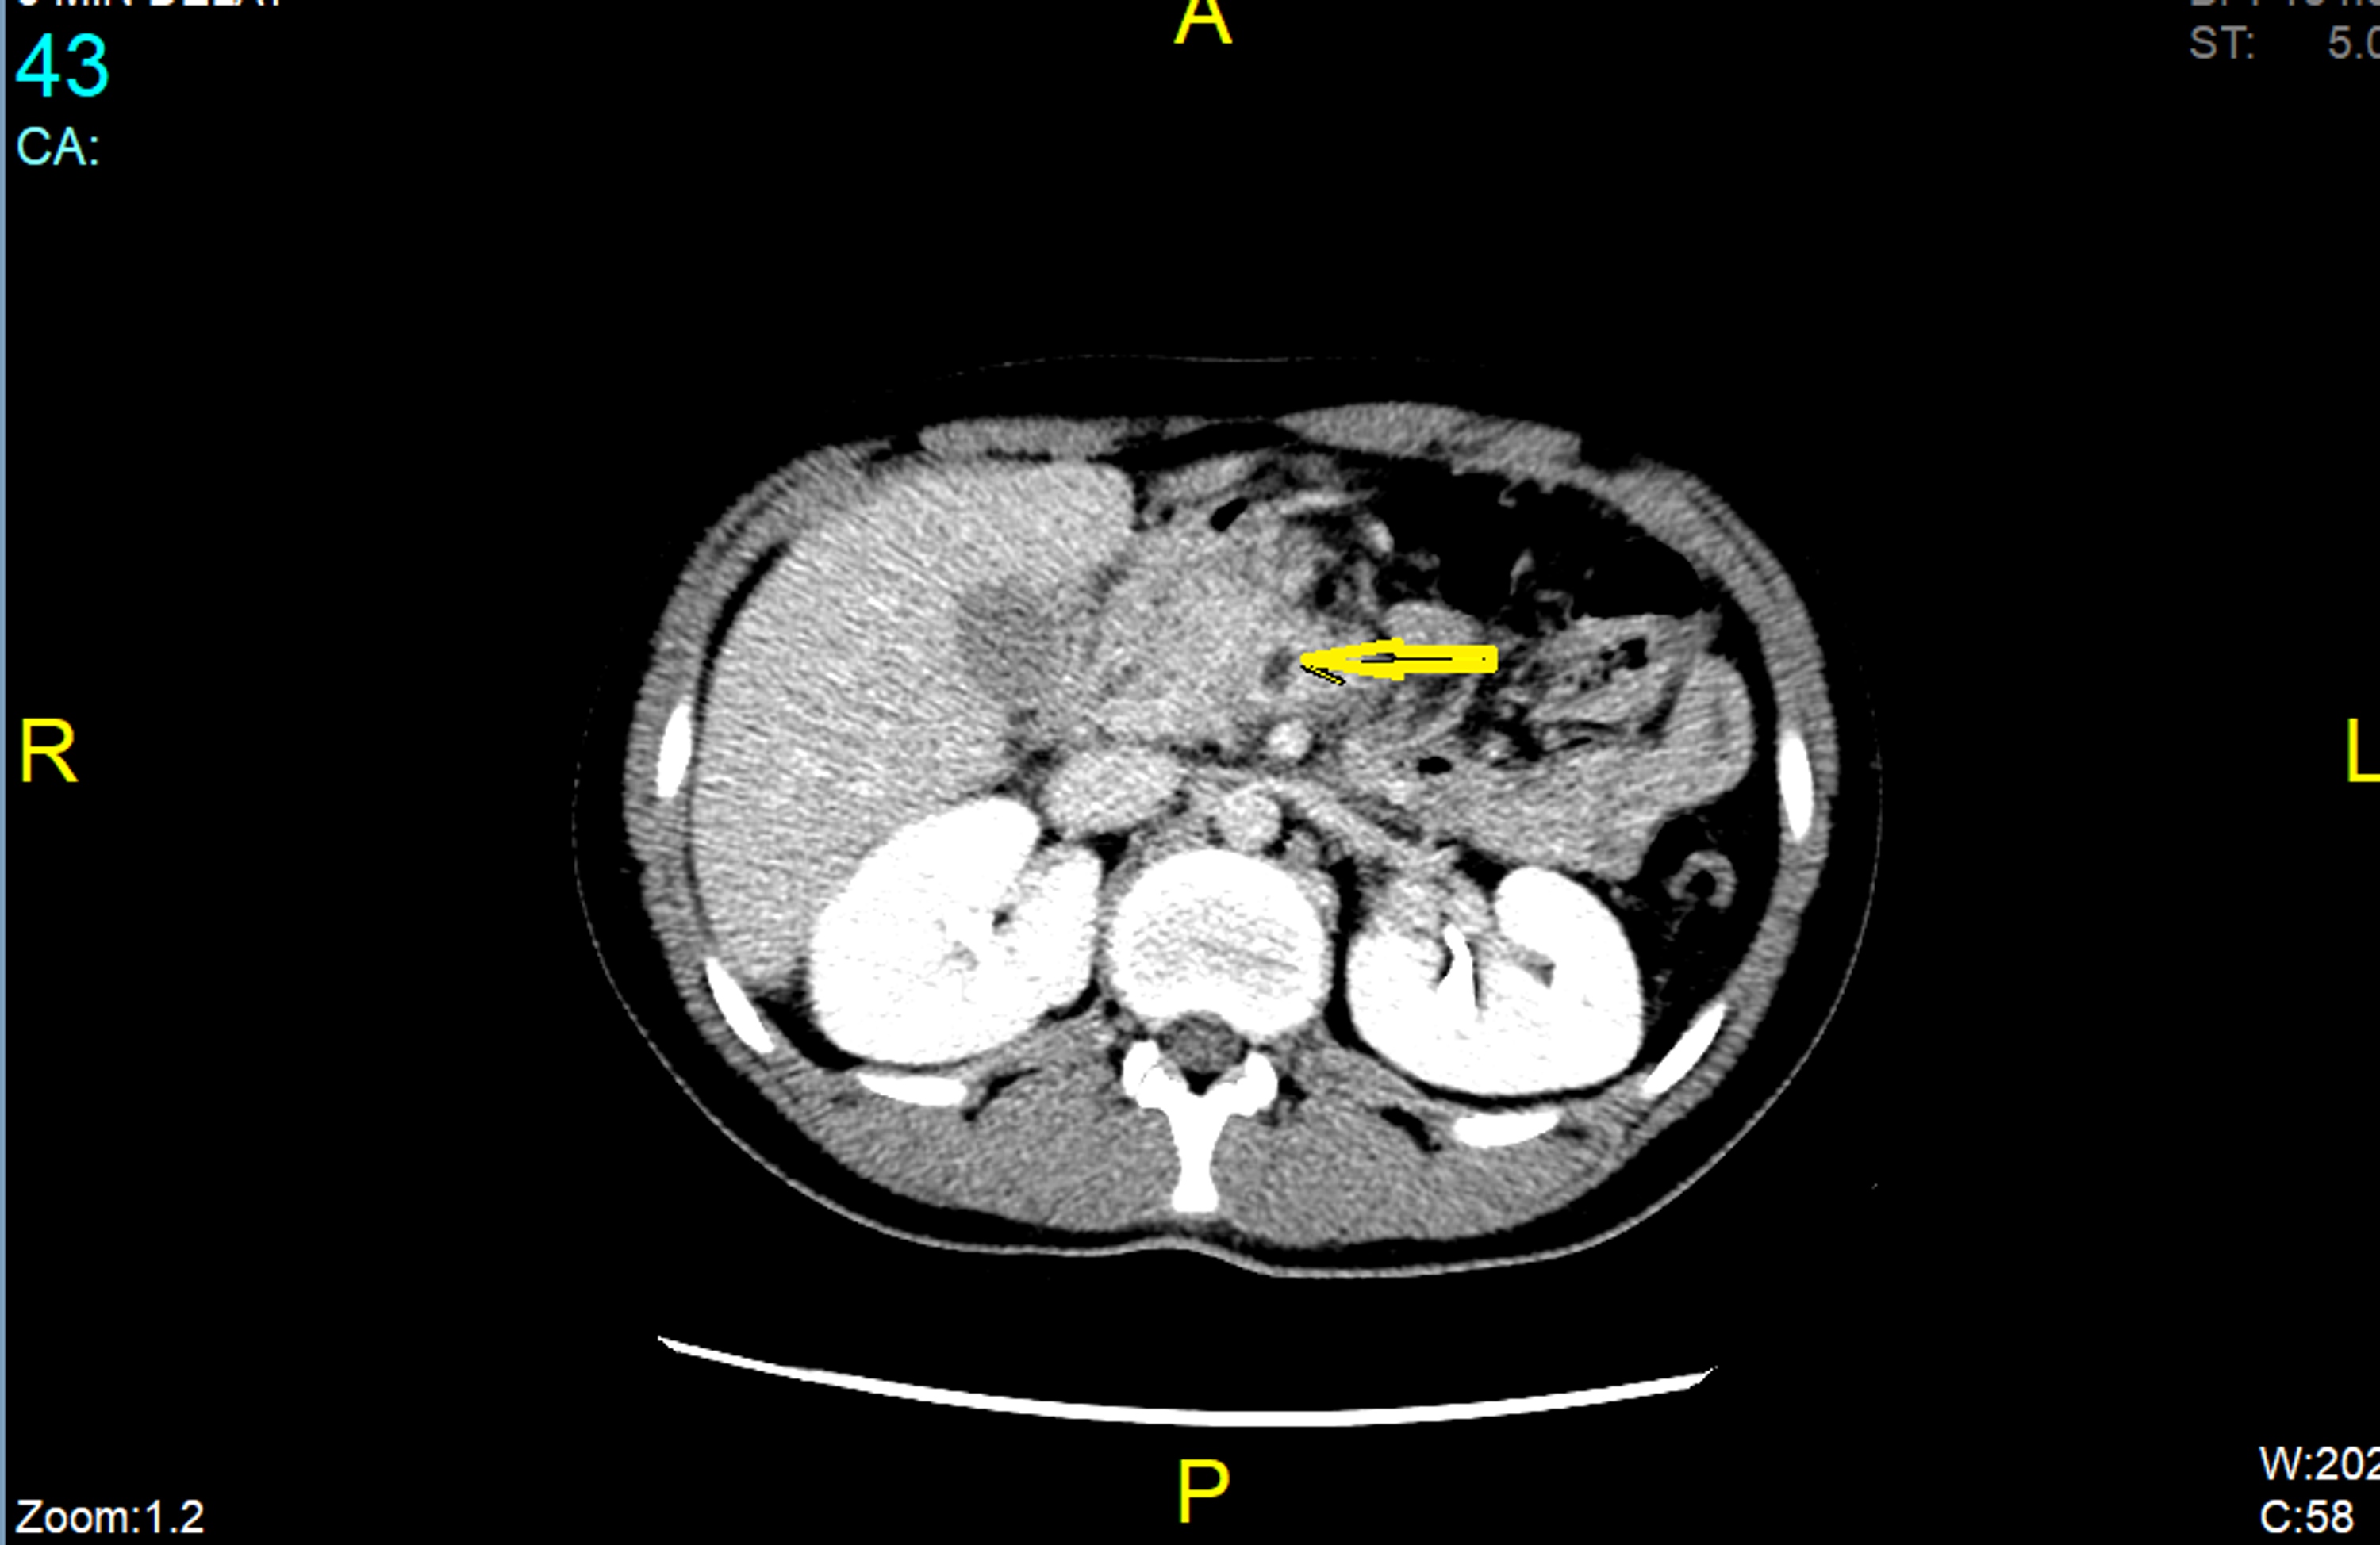

Superior Mesenteric Vein Thrombosis Causes. Venous complications usually manifest as thrombosis of the superior mesenteric or portal vein. The newer imaging techniques allow earlier diagnosis. Many of the diseases cause swelling inflammation of the tissues surrounding the veins and include. Acute mesenteric thrombosis will cause congestion of the bowel wall and may result in intestinal ischemia.

It can be either acute presenting commonly with abdominal pain or chronic presenting with features of portal hypertension. Signs and symptoms may overlap with those of many other diseases and thus diagnosis and treatment can be delayed. It is known that pancreatitis occurring with isolated superior mesenteric vein thrombosis SMVT alone is generally associated with a neoplasm or intra-abdominal sepsis. Primary mesenteric venous thrombosis is considered spontaneous and idiopathic whereas secondary mesenteric venous thrombosis is due to an underlying condition. In summary the most common predisposing factors in superior mesenteric vein thrombosis with radiologically occult cause are recent abdominal surgery infection and hypercoagulation. It causes intestinal damage or the death of intestinal.

Although no correlation was noted between risk factor and outcome the presence of bowel wall thickening and mesenteric congestion on CT or MR imaging was associated with the.

In summary the most common predisposing factors in superior mesenteric vein thrombosis with radiologically occult cause are recent abdominal surgery infection and hypercoagulation. Rial mesenteric ischemia with the ini-tial ischemic stage characterized by sudden-onset cramping abdominal pain. Online ahead of print. Although no correlation was noted between risk factor and outcome the presence of bowel wall thickening and mesenteric congestion on CT or MR imaging was associated with the. Both entities diagnostic and treatment guidelines share disparities and similarities that may.